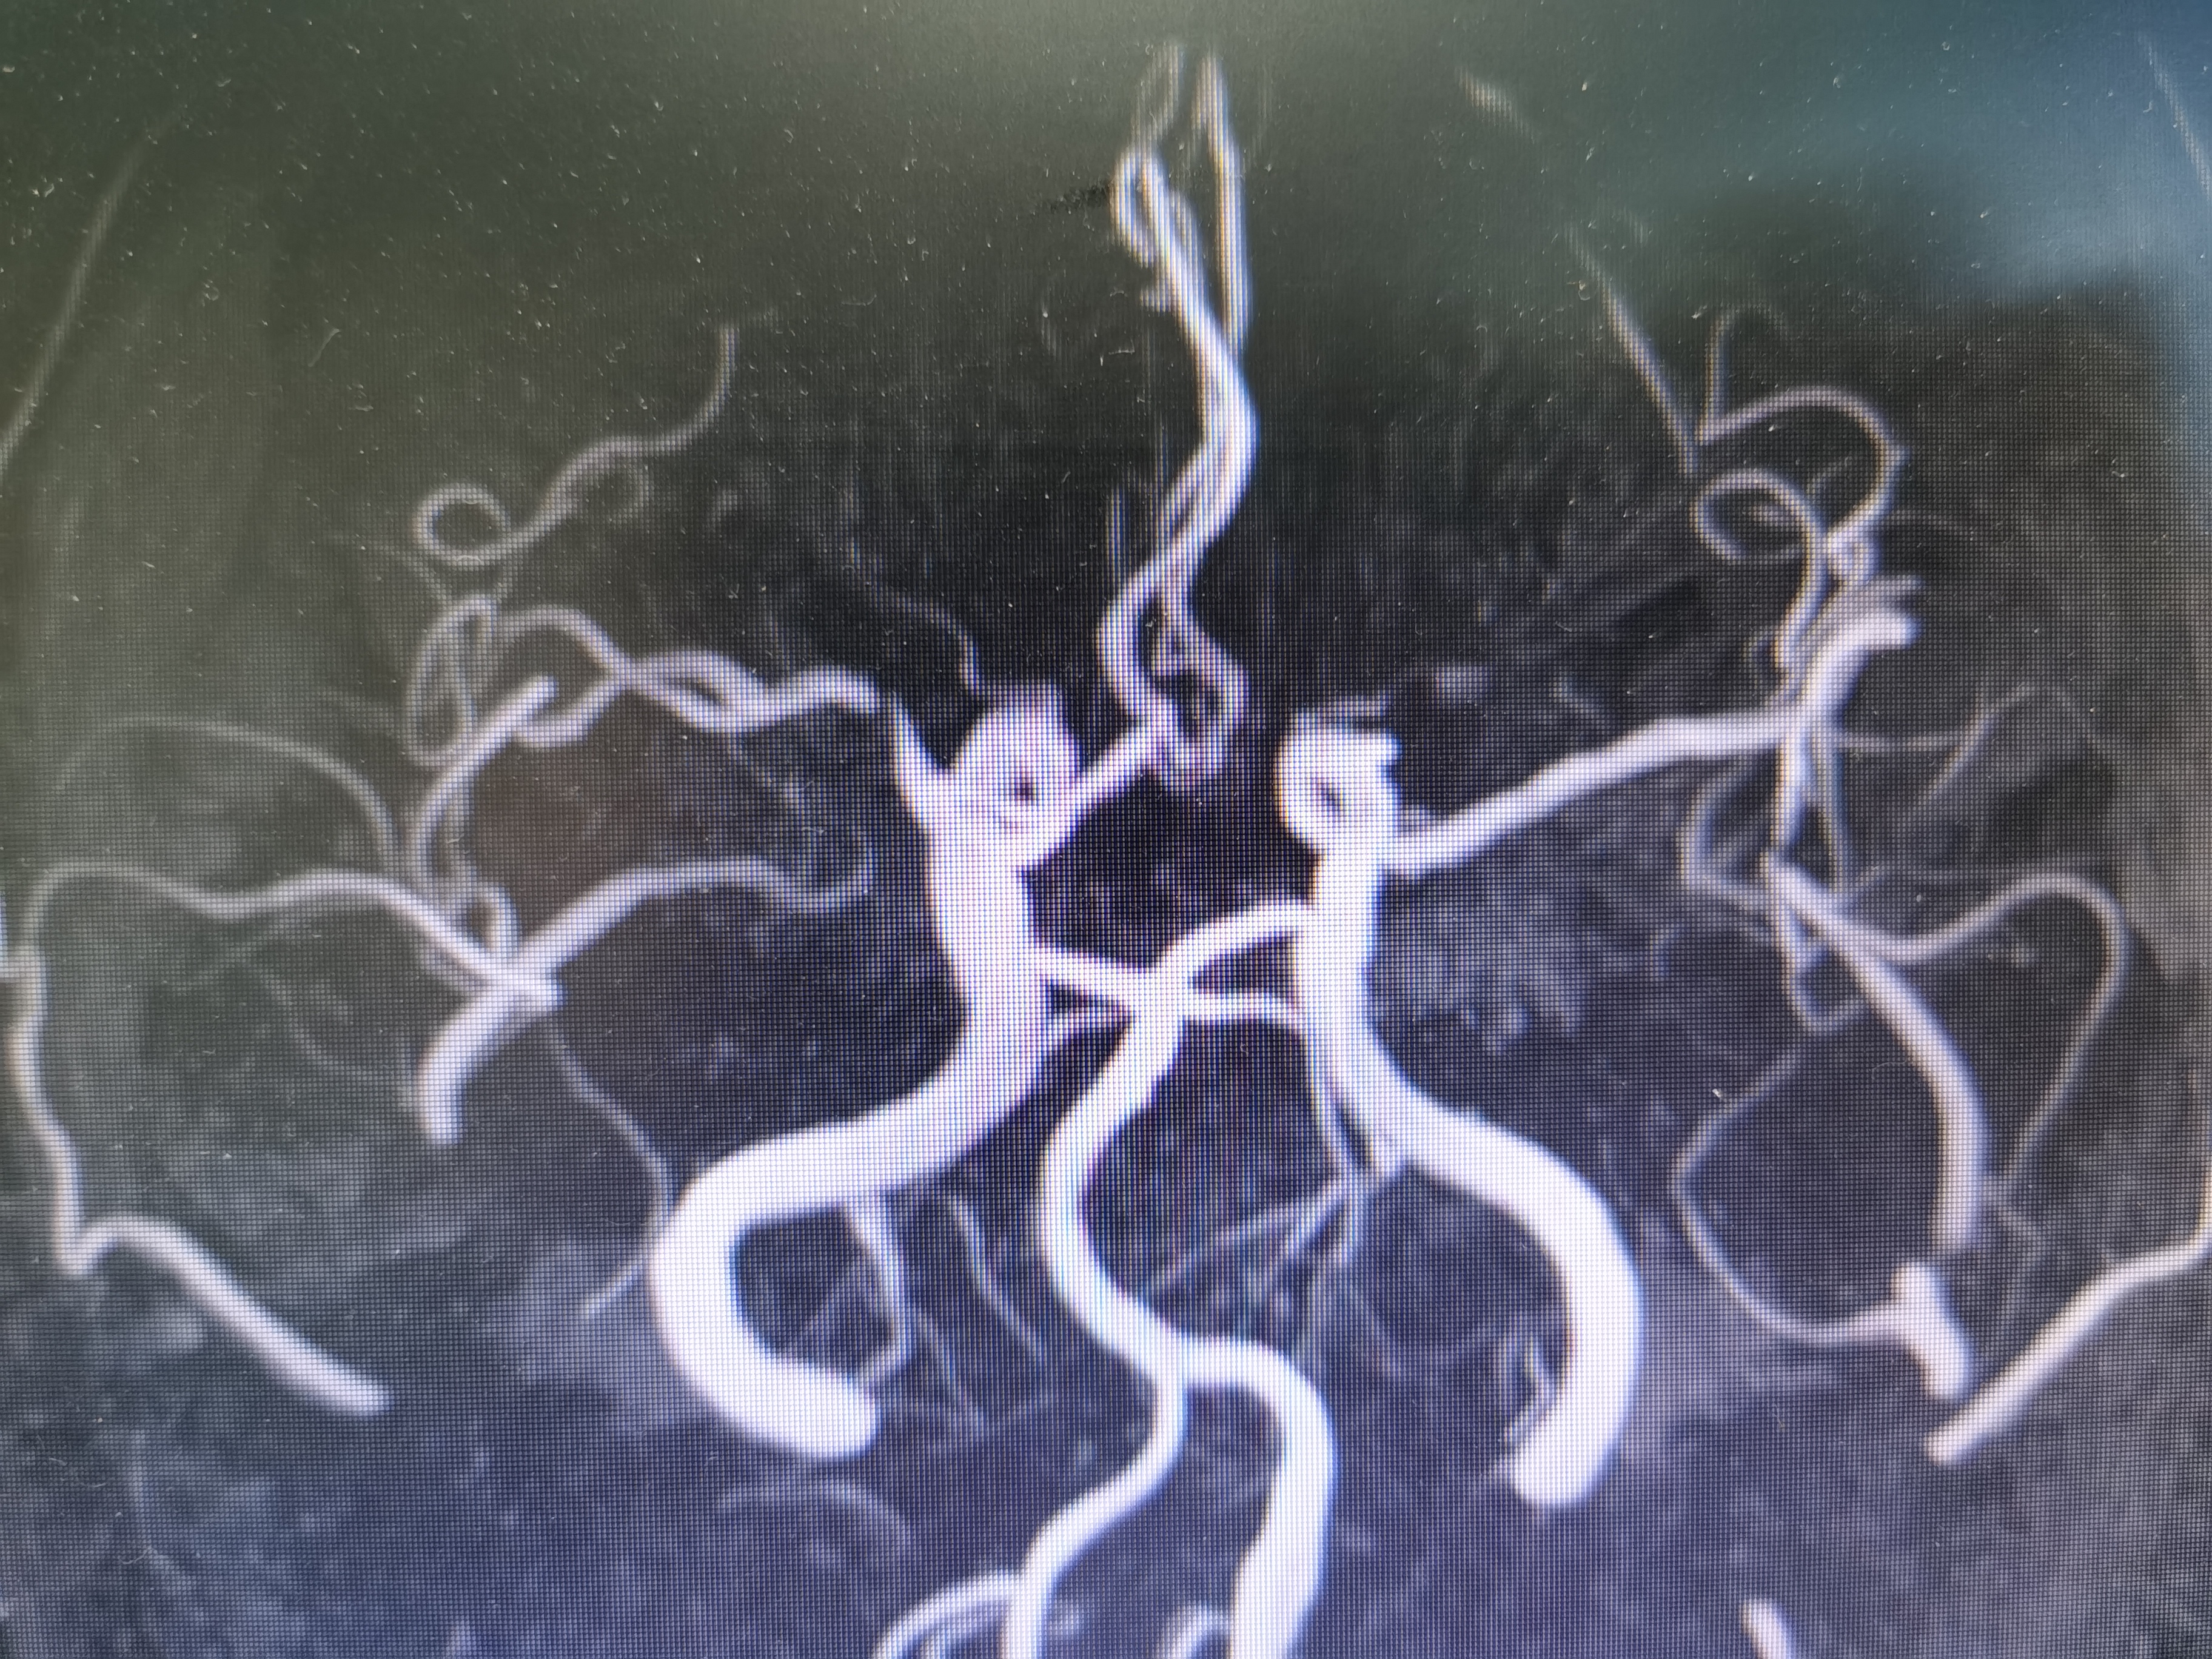

术前术后对比

球扩后造影见狭窄解除,豆纹动脉显影良好,远端血供改善,未见夹层征象。

正位造影见狭窄解除,颅内血流通畅。